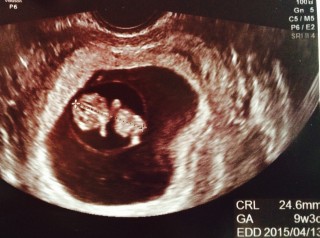

悪阻で大変な毎日。でも元気な二人の心拍が確認出来て私も主人も嬉しかったです。大きさも24.5mmと順調。次回は2週間後。待ちきれない~。

左上が頭でこれ手と足!と言われ確認できました。足がぴょこぴょこ動いててかわいかったです。CRL23ミリ。順調に育ってくれています!